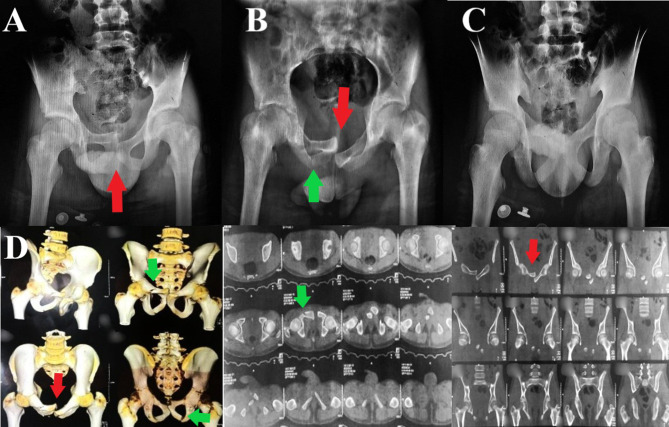

Urinary bladder entrapment or incarceration within pelvic fracture have been described in many reports in the literature, most of which were reported in adult patients. We describe a case of a 14-year-old boy presented with isolated locked symphysis pubis disruption after falling from a height. His initial evaluation was negative for any other associated injuries. The decision was made to treat him surgically by open reduction and internal fixation using a symphyseal plate; however, upon completing the Pfannenstiel incision, the surgeon faced a soft tissue mass hindering bony fragment dissection; upon careful examination, the soft tissue mass turned out to be entrapped urinary bladder within the symphyseal disruption. After careful soft tissue dissection, and with the help of Jungbluth distractor, the disruption was over-distracted, the bladder was freed entirely (which was intact) and reduced to its position, followed by the application of a symphyseal plate in a reduced symphysis pubis position. The patient did well postoperatively, and at three months follow up, the disruption and fracture united, and there were no urinary-related symptoms. Although rare, urinary bladder entrapment within an element of anterior pelvic fracture could be a reason for the difficult reduction; careful evaluation and steady soft tissue dissection are paramount for avoiding undue iatrogenic urinary bladder injury.